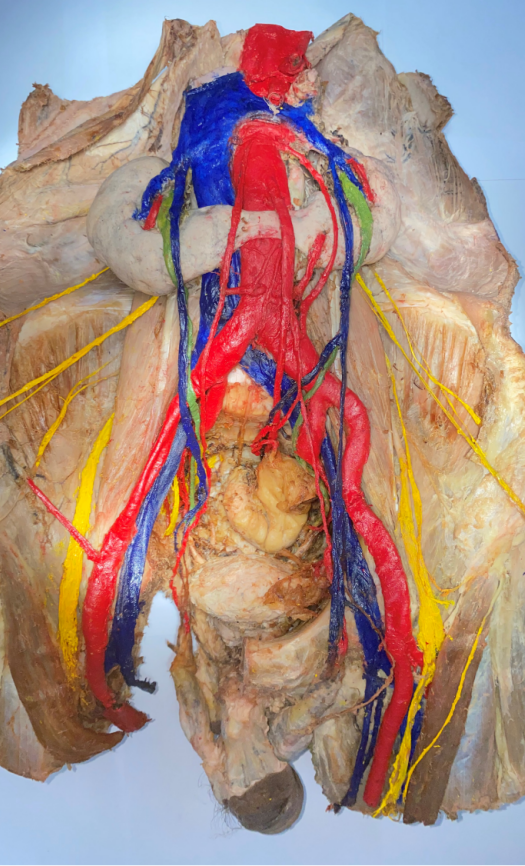

《两肾相连囊肿生,腹有斑斓隙自华》